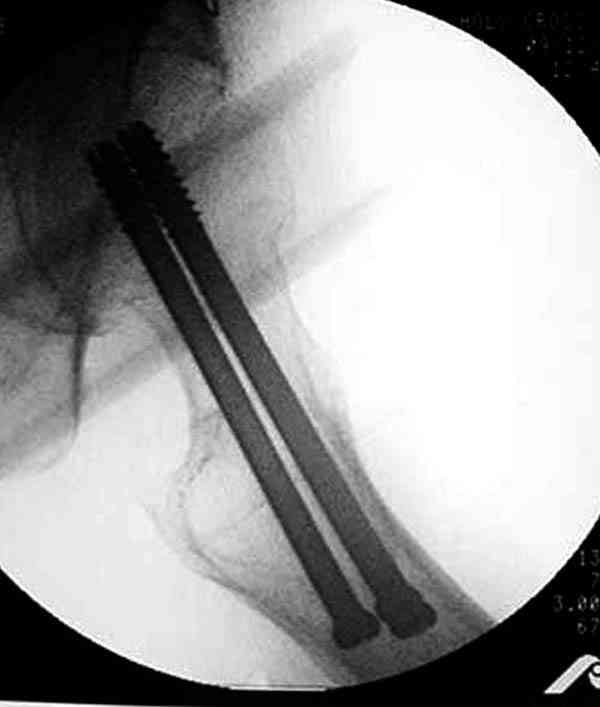

На Московской конференции в ноябре была продемонстрирована удивительная методика профилактического армирования шейки бедра у пациенток с остеопорозом и переломом контрлатеральной шейки в анамнезе.Странно, но дискуссии это сообщение не вызвало.Кто что думает об этом?

Спасибо, Антон. Я автор того сообщения по профилактическому армированию шейки бедренной кости, которое прозвучало на конференции, посвященной 50-летию создания АО. Мне тоже хотелось услышать вопросы по теме. Мы травматологи-ортопеды в первую очередь хирурги, а не терапевты. Почему в вопросе профилактики и лечения остеопороза мы ограничиваемся только консервативными методами лечения? Как можно практически научить больного не получать травмы, когда немало случаев возникновения переломов даже в постели. Первоначально идея армирования ШБК многих, при ком я озвучивал ее, шокировала, затем возникала дискуссия и большинство поддерживали эту идею. Мне бы очень хотелось развернуть дискуссию на странице этого сайта.

Уважаемый Антон! У меня было всего три клинических наблюдения, снимки были продемонстрированы на московской конференции. Количества этих снимков хватило для подачи заявки, а затем и получения патента на изобретение. В свое время РОСПАТЕНТ потребовал подтверждения методики клиническими наблюдениями. У одной из больных действительно произошла повторная травма, и произошел подвертельный перелом на стороне армированной шейки бедренной кости (см. снимки). Это подтвердило основную идею изобретения - была сохранена и головка, и армированная шейка бедренной кости. Но тут не обошлось безпроблем. Анестезиологи отказались давать наркоз, а провести остеосинтез под м/а пластиной и винтом DHS не согласилась больная. Дальнейшее лечение скелетным вытяжением. На контр. Рентгенограмме через 2 месяца признаки формирования костной мозоли. Повторных обращений двух других пациентов не было. Для более детальных исследований и выводов необходимо значительно большее количество клинических наблюдений. Такие исследования могли быть проведены в условиях клиник медуниверситета. Напомню, я работаю в травмотделении провинциальной городской больницы. Насчет экспертов страховых компаний, так пусть они выскажут свое мнение. Армирование кости - это плановые операции по желанию больного, какие здесь могут быть противоречия? На армирование все больные, к моему удивлению, согласились довольно легко и сразу, поэтому остеосинтез и армирование были проведены в течение одной операции. С уважением А.М.

Кстати, очень сомнительна остеопорозность на правом оперированном бедре, отсутствует данные денситометрии с индексом остеопороза.

Коллега Челноков прав, здесь еще имеется риск перелома за счет ослабления латерального кортекса. Во время установки канюлированных шурупов за редким исключением спица вводится с одного раза, множественные попытки ослабляют латеральный кортекс, что станет источником перелома в этом месте.

В идеале для профилактики рефрактуры шурупы надо вводить не больше, чем под 130 градусным углом и не ниже уровня малого вертела.

Насчет биомеханических преимуществ одного шурупа тоже возникает вопрос. Если придерживаться канонов механики, для перелома шейки необходимо 3 паралельных шурупа, расположенных ближе к кортикальному слою шейки.

Здесь случай перелома из-за ослабления латерального кортекса через 3 недели после операции на шейке. Шурупы были установлены под большим углом, слабый латеральный кортекс не выдержал нагрузку.